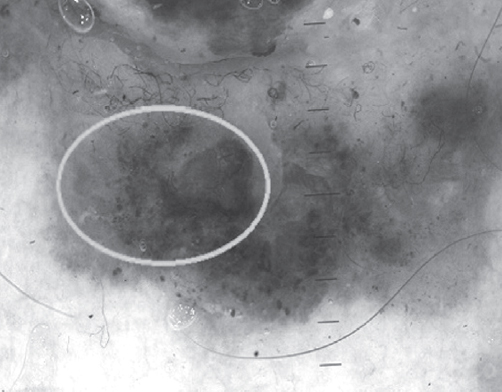

Анализ частоты встречаемости десяти признаков меланоцитарных новообразований при проведении дерматоскопии 34 гистологически верифицированных новообразований кожи (11 меланом и 23 меланоцитарных невуса) показал, что признак «асимметрия пигментации и строения» (рис. 1) присутствовал в меланомах в 11 случаях, в невусах — в 8 случаях. Признак «атипичные глобулы» присутствовал в меланомах в 7 случаях, в невусах — в 9 случаях. Признак «асимметричные полосы» присутствовал в меланомах в 6 случаях, в невусах — в 8 случаях. Признак «атипичная пигментная сеть» (рис. 2) присутствовал в меланомах в 8 случаях, в невусах — в 17 случаях. Признак «бело-голубая вуаль» присутствовал в меланомах в 10 случаях, в невусах — в 4 случаях. Признак «асимметричные зоны гиперпигментации» (рис. 3) присутствовал в меланомах в 11 случаях, в невусах — в 18 случаях. Признак «зернистость» присутствовал в меланомах в 4 случаях, в невусах — в 1 случае. Признак «рубцовоподобные очаги гипопигментации» (рис. 4) присутствовал в меланомах в 4 случаях, в невусах — в 2 случаях. Признак «белые блестящие полосы» присутствовал в меланомах в 5 случаях, в невусах не встречался. Признак «негативная пигментная сеть» присутствовал в меланомах в 1 случае, в невусах — в 2 случаях.

Рис. 3. Асимметричные зоны гиперпигментации

Оценивая полученные результаты можно констатировать, что наибольшую ДЧ имели следующие признаки: асимметрия пигментации и строения (100 %), асимметричные зоны гиперпигментации (100 %) и бело-голубая вуаль (90,9 %). Наибольшую ДС имели следующие признаки: белые блестящие полосы (100 %), зернистость (95,6 %) и рубцовоподобные очаги депигментации (91,3 %). Наибольшую ДЭ имели следующие признаки: бело-голубая вуаль (86,8 %), асимметрия пигментации и строения (82,6 %) и белые блестящие полосы (72,8 %).